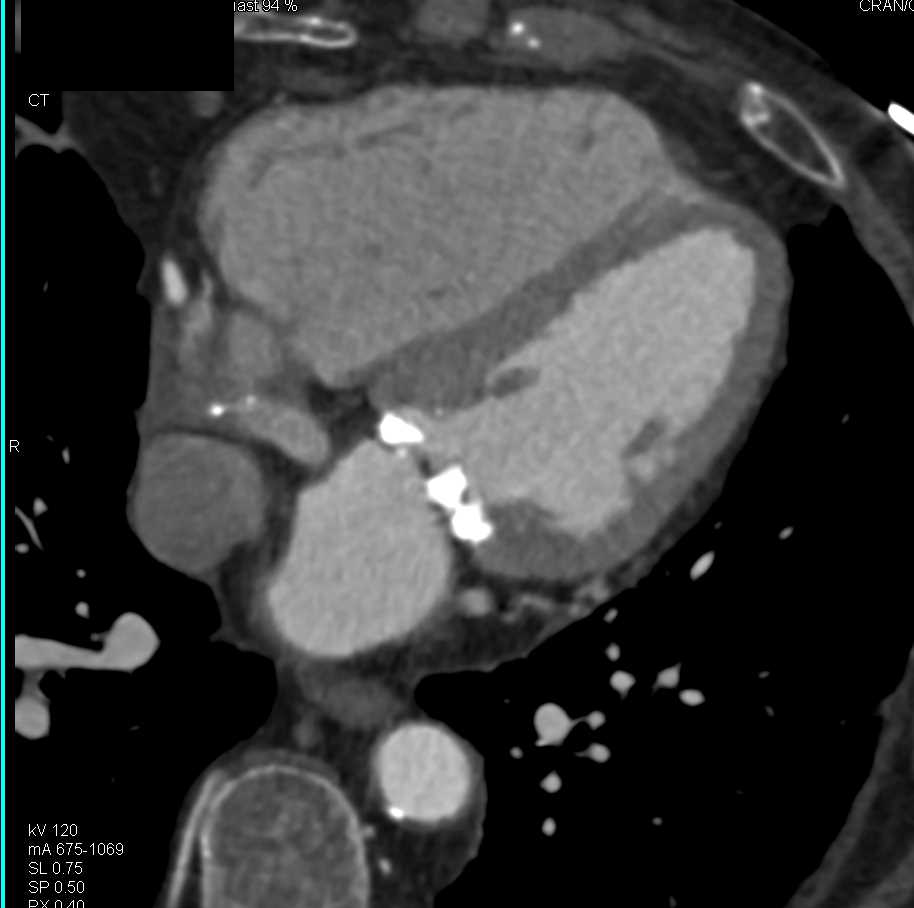

3D of Left Internal Mammary Artery (LIMA) and Venous Grafts